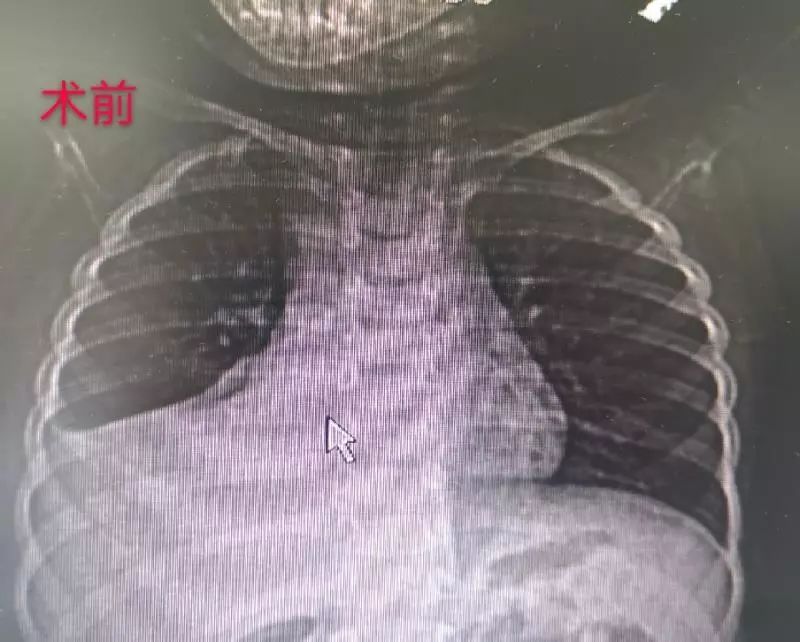

18岁少女胸骨凹陷心脏差点被压扁

漏斗胸是一种前胸部凹陷畸形,医学上属于胸外科诊疗范畴;而脊柱侧弯是

漏斗胸图片